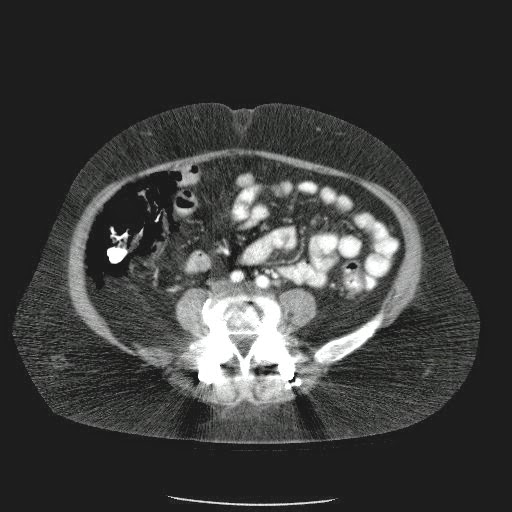

Caso Interesante #4

Adulto masculino, 1 semana de fiebre y malestar general.

¿Dónde esta ubicado el hallazgo?